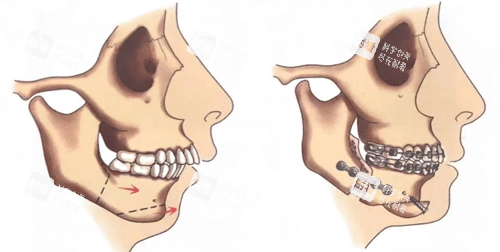

小牛的故事,堪稱“頜面逆襲教科書(shū)”。她從小因上頜發(fā)育過(guò)度、下巴后縮被同學(xué)起外號(hào)“月亮臉”,工作后因形象自卑不敢參加社交活動(dòng)。2024年初,她找到艾偉健醫(yī)生,經(jīng)過(guò)詳細(xì)評(píng)估后,醫(yī)生制定了“上下頜根間截骨術(shù)+頦成型術(shù)”方案。術(shù)后3個(gè)月復(fù)查時(shí),她的臉型從“凸面型”變成流暢的“直面型”,連同事都追問(wèn)“是不是偷偷去做了醫(yī)美”。

“價(jià)格差異主要看手術(shù)復(fù)雜度?!卑瑐ソ〗忉專热缧∨5牟±龑儆凇半p顎+頦成型”,涉及上下頜骨截骨、下巴重塑,操作時(shí)長(zhǎng)超4小時(shí),費(fèi)用自然更高。但相比北京、上海同類手術(shù),廣州的價(jià)格普遍低20%-30%,性價(jià)比更突出。